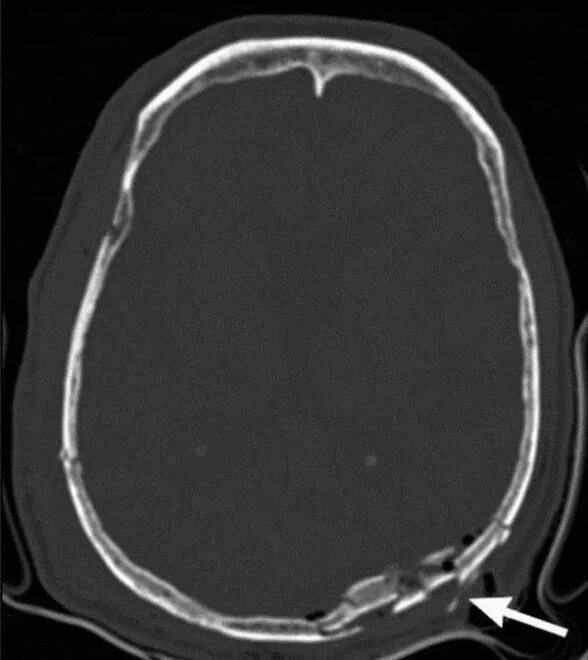

Оскольчатый перелом черепа